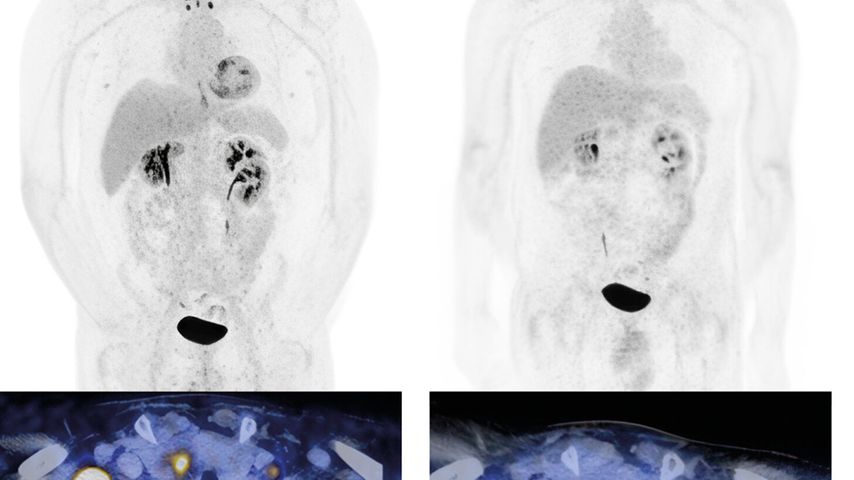

Beim nichtkleinzelligen Lungenkarzinom im Stadium IV ohne Treibermutationen ergeben sich in der Praxis zentrale Fragestellungen aus der Selektion der Erst- und Zweitlinientherapie sowie ...